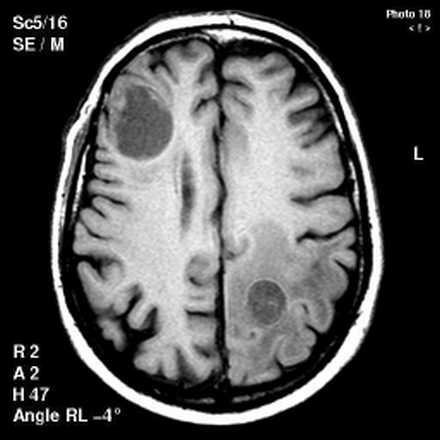

41+ Brain Tumor Classification Radiology PNG. Who brain tumour classification has been updated in 2016. Primary brain tumors are derived from brain cells and often have less mass effect for their size than you would expect, due to their infiltrative growth.

We review brain tumor radiologic studies (eg, imaging interpretation) through computational second, recent breakthroughs in deep learning with applications in radiology, such as lung nodule. The 2016 world health organization classification of tumors of the central nervous system is both a conceptual and practical advance over its 2007 predecessor. A listing of most of the tumors that occur in the brain or its surrounding structures is presented here. Primary brain tumors are typically seen in a single region, but some.